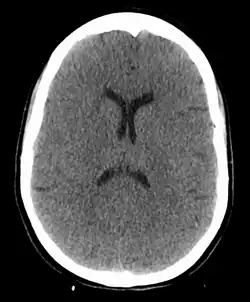

The cause of death in hanging depends on the conditions related to the event. When the body is released from a relatively high position, the major cause of death is severe trauma to the upper cervical spine. The injuries produced are highly variable. One study showed that only a small minority of a series of judicial hangings produced fractures to the cervical spine (6 out of 34 cases studied), with half of these fractures (3 out of 34) being the classic "hangman's fracture" (bilateral fractures of the pars interarticularis of the C2 vertebra).[23]

The side, or subaural knot, has been shown to produce other, more complex injuries, with one thoroughly studied case producing only ligamentous injuries to the cervical spine and bilateral vertebral artery disruptions, but no major vertebral fractures or crush injuries to the spinal cord.[24]

In the absence of fracture and dislocation, occlusion of blood vessels becomes the major cause of death, rather than asphyxiation. Obstruction of venous drainage of the brain via occlusion of the internal jugular veins leads to cerebral oedema and then cerebral ischemia. The face will typically become engorged and cyanotic (turned blue through lack of oxygen). Compromise of the cerebral blood flow may occur by obstruction of the carotid arteries, even though their obstruction requires far more force than the obstruction of jugular veins, since they are seated deeper and they contain blood in much higher pressure compared to the jugular veins.[25]